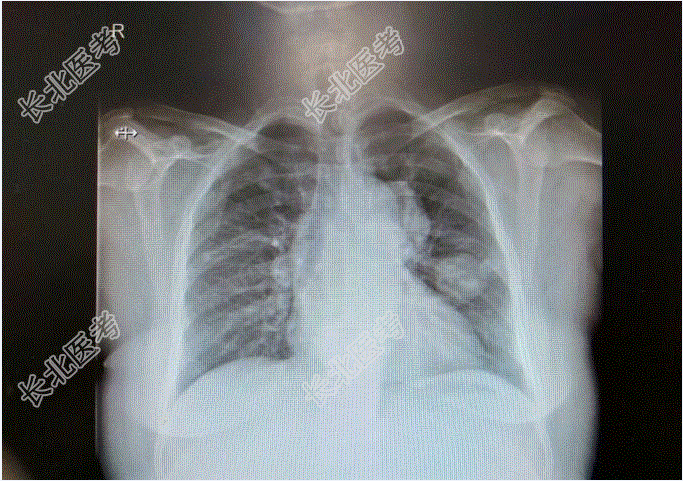

既往史:患者于25岁时足月顺产一健康活婴;于35岁时足月剖宫产一健康活婴;剖宫产后10月因“葡萄胎”行清宫术3次;2015-02-05再次于外院行清宫术。已婚,2-0-3-2,患者于25岁时足月顺产一健康活婴;于35岁时足月剖宫产一健康活婴。15岁,月经规律,4-5/40,量中,痛经(-),闭经4年。查体:T:36.9℃,P:88次/分,R:18次/分,BP:140/90/mmHg。妇科检查:外阴:(-);阴道:通畅;宫颈:光滑;子宫:前位,增大如孕8周,活动可。双附件(-)。辅助检查:胸片:两肺多个结节影,拟转移瘤,两肺纹理增多,主动脉迂曲。血常规:白细胞计数7.30×10⁹/L,血红蛋白125g/L,血小板计数405↑×10⁹/L。

查β-HCG>150000mIU/ml;彩超提示:1、侵袭性葡萄胎待排2、子宫内膜增厚伴宫腔积液3、宫颈肥大伴回声欠均匀4、盆腔积液;2023-1-27外院胸部CT提示:1、两肺多发小结节,考虑转移。再次于行清宫术,术后血HCG下降:160000mIU/ml,术后病理示:镜下见蜕膜、出血、坏死组织中见细胞滋养叶细胞及合体滋养叶细胞。滋养叶细胞增生伴轻度异型,未见确切绒毛结构。患者自诉此次清宫术后血HCG一度下降至50000mIU/ml左右,后复查HCG再次上升至β-HCG:89000mIU/ml。外院会诊后考虑为“绒癌”并于予5Fu1.5静滴8小时d1-8,放线菌素-D0.4mg静滴d1-8化疗。化疗后:β-HCG91000mIU/ml,2023-4-1:β-HCG:90000mIU/ml,2023-4-1外院CT提示胸部多发转移灶较前增大。遂于2017-4-14至我院就诊住院治疗,2023-04-20起给予5-Fu+KSM方案化疗:5-FU(1.5gd1-d4,1.75gd5-d8)+KSM(200μgd1,400μgd2-d8),观察无明显化疗副反应。2023-5-6于外院复查血常规正常,β-HCG2597.36mIU/mL。第二次化疗后至今患者无咳嗽咳痰,恶心呕吐,腹痛腹泻等不适症状。现患者为求进一步诊治,门诊拟“恶性葡萄胎”收治入院。